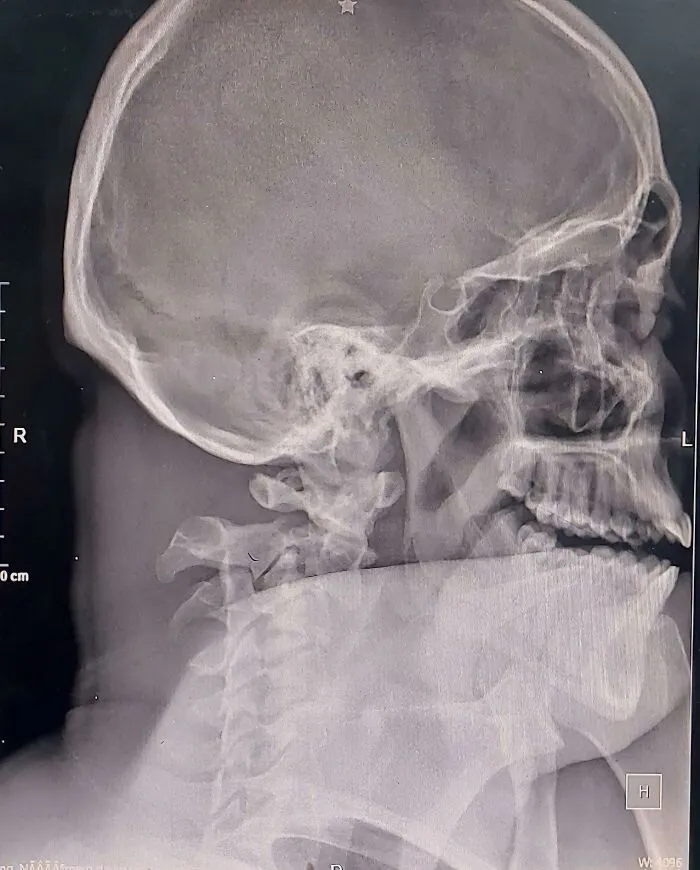

20. Мужчина с переломом шейного отдела позвоночника как-то сумел приехать в отделение интенсивной терапии самостоятельно, на такси